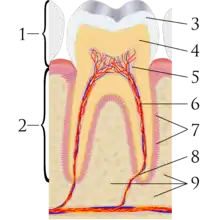

A tooth is composed of an outer shell of calcified hard tissues (from hardest to softest: enamel, dentin, and cementum), and an inner soft tissue core (the pulp system), which contains nerves and blood vessels. The visible parts of the teeth in the mouth – the crowns (covered by enamel) – are anchored into the bone by the roots (covered by cementum). Underneath the cementum and enamel layers, dentin forms the bulk of the tooth and surrounds the pulp system. The part of the pulp inside the crown is the pulp chamber, and the central soft tissue nutrient canals within each root are root canals, exiting through one or more holes at the root end (apical foramen/foramina). The periodontal ligament connects the roots to the bony socket. The gingiva covers the alveolar processes, the tooth-bearing arches of the jaws.[42]:1–5